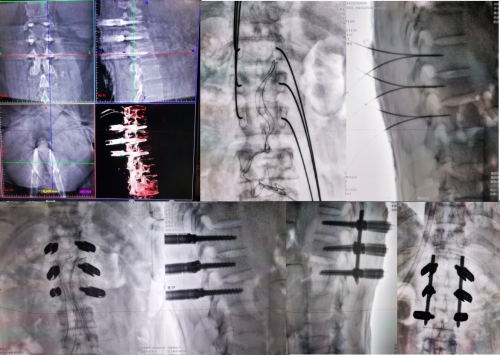

(手术后)

本次接受远程骨科机器人手术的是一位因高处坠落伤导致腰椎多节段爆裂骨折的男性患者,其中尤以L1椎体最严重,骨折块移入椎管内引起脊髓受压,万幸的是该患者没有明显的脊髓损伤表现。为了更微创同时更安全的解决患者病痛困扰,经邓幼文主任手术团队讨论,并与北京积水潭赵经纬主任沟通交流后,决定采用“两地协同,远程机器人诊疗”的方案,由湘雅三医院脊柱外科携手北京积水潭医院机器人远程手术中心,通过5G通信技术结合机器人开展远程手术。手术当天,邓幼文主任、李志跃主任、谭伟主治医师及刘仁峰总住院医师组成了湘雅三医院手术团队与北京积水潭医院赵经纬主任及其团队,在积水潭医院机器人远程手术中心实时连线交流指导,经过两个团队的精诚合作,手术得以顺利的开展,患者麻醉醒来即感痛症状缓解明显,检查并无神经损伤表现。